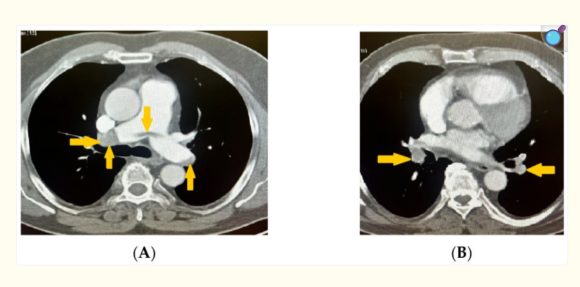

Случаят представлява първо описание на нова мутация в гена FGF23 (c.202A>G, p.Thr68Ala) при пациент с изключително рядко наследствено заболяване – хиперфосфатемичен вариант на туморна калциноза, усложнен с тежки съдови аневризми и тромбози.

Научната й дейност демонстрира последователен интерес към взаимодействието между генетичните фактори и клиничната изява на заболяванията. В своята последна публикация, озаглавена „A Sole Case of Concurrent Arterial and Venous Thromboses with Massive Pulmonary Embolism and Carriage of Four Genetic Polymorphisms: Factor V Leiden, PAI-1 4G/5G, MTHFR C677T, and ACE I/D—A Case Report“, тя предлага нова интерпретация на възможните полигенни механизми, свързани с тромботичните процеси, допринасяйки за по-задълбоченото разбиране на молекулярните основи на тромбозата и развитието на персонализираната медицина.